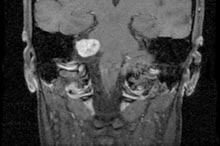

Diese, jeweils selbstständigen Leistungserbringer im Gesundheitswesen haben sich zum Ziel gesetzt, Sie durch diese gemeinsame Internetpräsenz über die Diagnose, Behandlung und Entfernung von Tumoren der Schädelbasis, des Kleinhirnbrückenwinkels, der Augenhöhle und des Sehnervs zu informieren und stehen Ihnen als behandelnde Ärzte zur Verfügung.